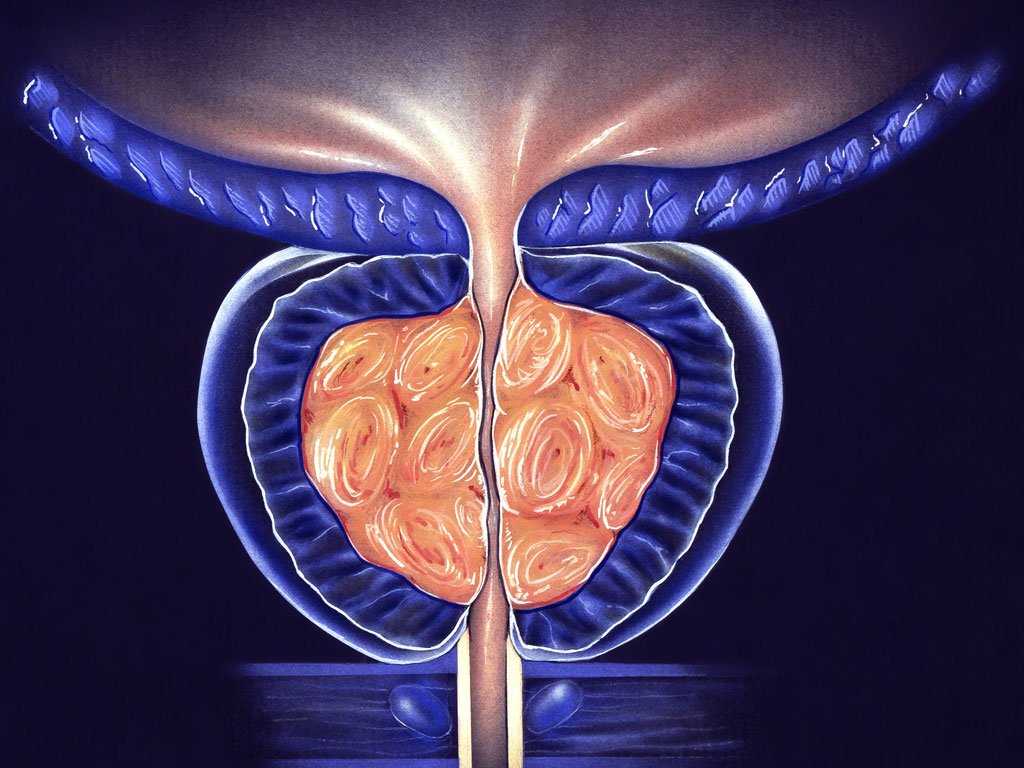

Memahami dengan baik kemungkinan bahaya radang prostat adalah langkah penting untuk kesehatan laki-laki. Penyakit ini membutuhkan perhatian yang serius agar tidak memberikan efek buruk pada sistem reproduksi.

Dampak Buruk dan Bahaya Radang Prostat yang Menyebar ke Ginjal

Infeksi yang menetap pada area prostat mampu menjalar menuju organ ginjal melalui saluran kemih. Fenomena ini seringkali mengakibatkan kerusakan jaringan ginjal yang bersifat menetap dan membahayakan kesehatan tubuh.

Pembentukan Abses sebagai Komplikasi Serius Akibat Peradangan Kelenjar Prostat

Kumpulan nanah atau abses dapat terbentuk di dalam jaringan prostat yang mengalami peradangan hebat. Munculnya abses ini biasanya menyumbat saluran kencing sehingga menimbulkan rasa sakit luar biasa hebat.

Risiko Retensi Urin Akut Mengenali Bahaya Radang Prostat Sejak Dini

Pembengkakan kelenjar yang membengkak menekan saluran uretra sehingga menghambat aliran pembuangan air seni harian. Akibatnya kandung kemih tidak mampu mengosongkan diri sepenuhnya meski penderita sudah berusaha mengejan kuat.